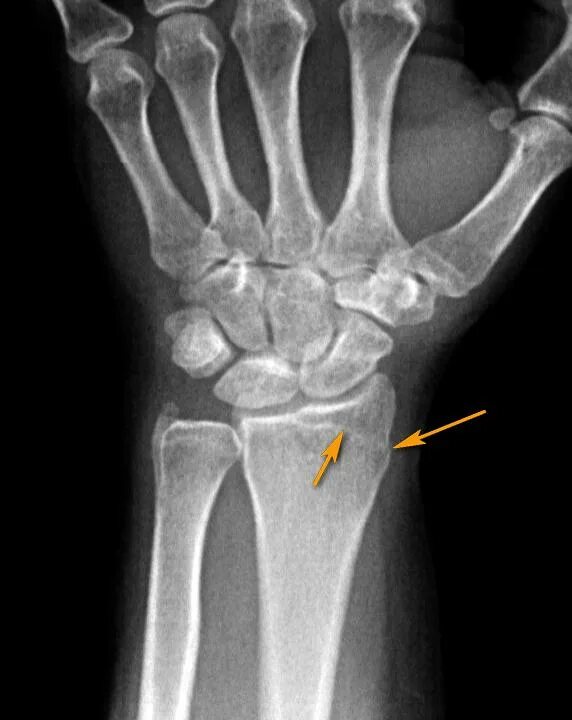

Перелом лучезапястного сустава мкб 10